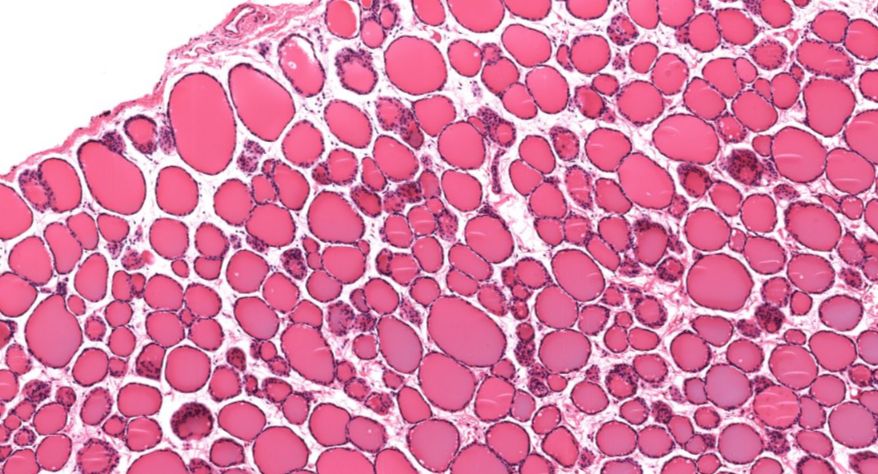

甲状腺

1.全景图